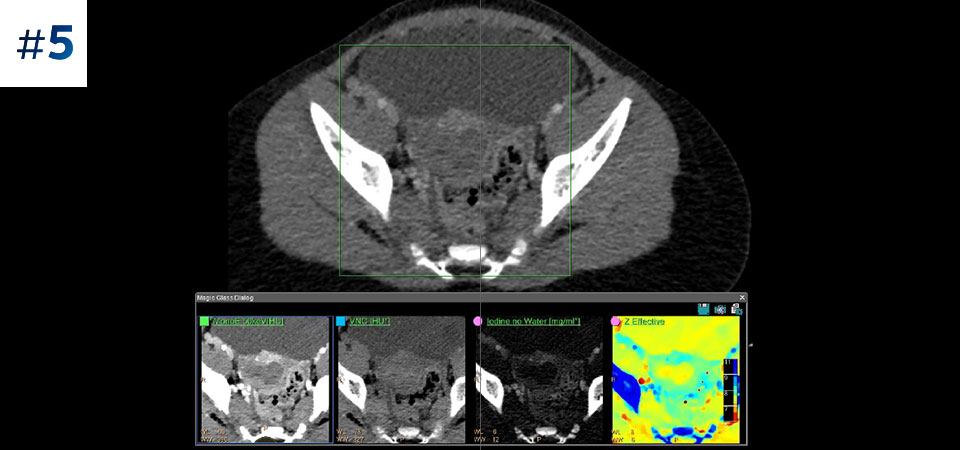

With detector-based spectral, you acquire multiple layers of data—conventional and spectral—within a single exposure and without special scan modes for improved tissue characterization and visualization.

Reduced follow-up exams Improved tissue characterization and visualization may reduce the need for follow-up scanning for sub-optimal exams and incidental findings.

Can you solve the mystery diagnosis using spectral?

Go beyond conventional CT. See how layers of spectral-detector results can enhance your diagnostic confidence.